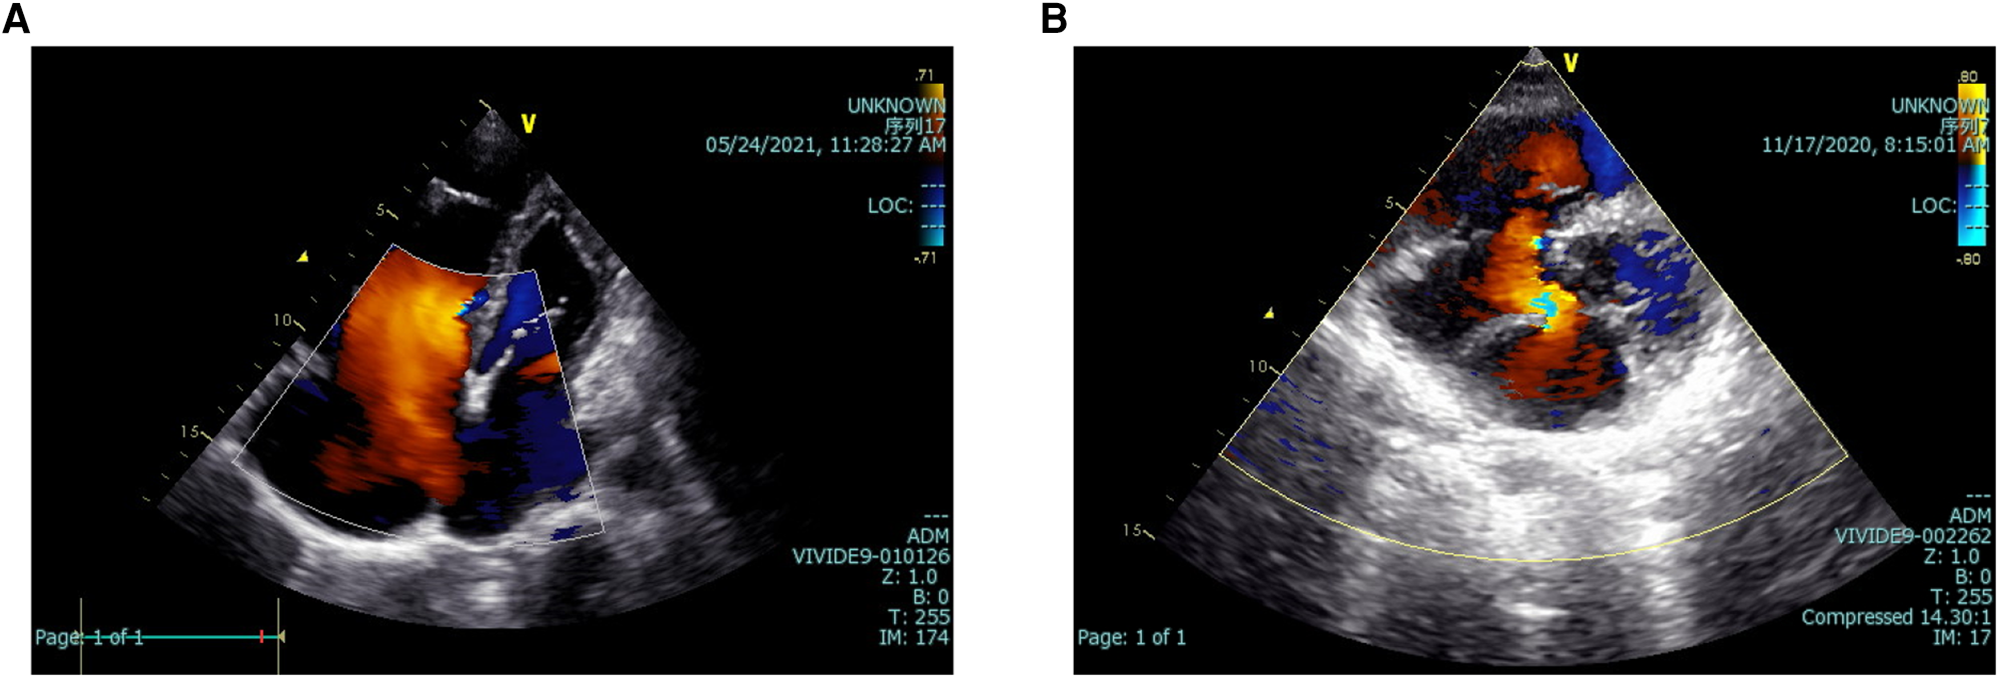

In addition, Figures 2, 3 depict imaging criteria for the basic materials. Meanwhile, Figure 2 shows the echocardiogram of secundum (Figure 2A), and primum (Figure 2B) ASD, in which doppler ultrasound shows the direction and location of atrial shunting and the defect location. The defect of the primum ASD is closer to the ventricle.

Figure 2

Echocardiograms of two kinds of ASD. The echocardiogram of secundum (A), and primum (B) ASD. Doppler ultrasound shows the direction and location of atrial shunting and the defect location. ASD, atrial septal defect.